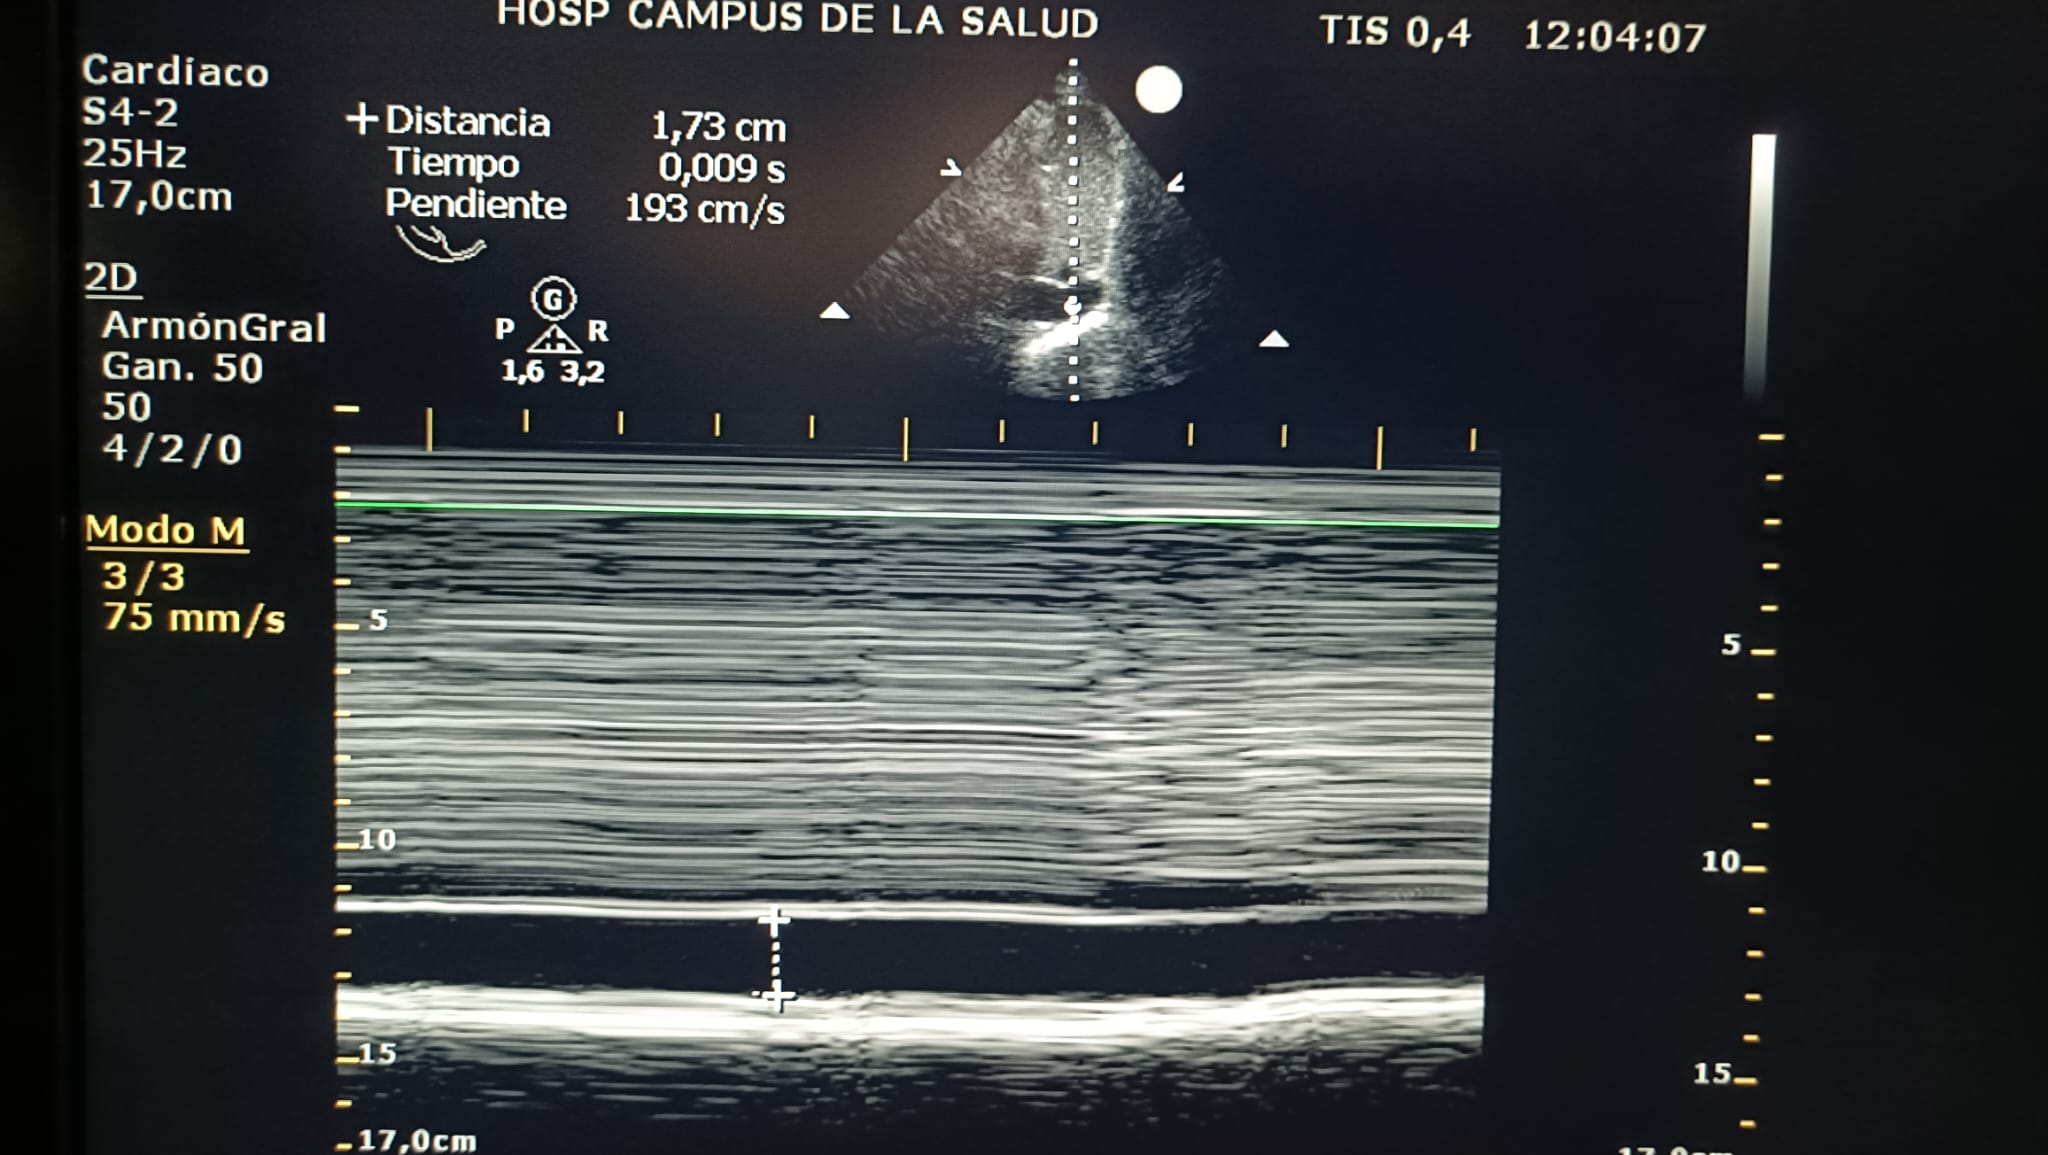

Diámetro VCI: 1.73

Colapso VCI: 10%

Grado VEXUS: 0

Estadio VEXUS: No evaluable